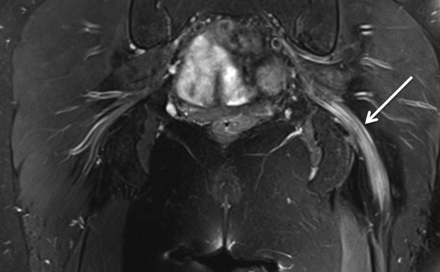

38岁的女人出现急性发作剧烈疼痛的吸海洛因后左小腿和脚。在考试,她远左下肢无力和足踝反射缺席。EMG在8周建议一个轴突坐骨神经病变。艾滋病毒检测是负面的。肌酸激酶、红细胞沉降率和c反应蛋白是正常的。MRI显示突出的水肿和扩大的左侧坐骨神经不对比度增强(图)。她收到了每周注入静脉甲基强的松龙导致改善她的症状和核磁共振的发现。公认的神经肌肉急性并发症海洛因使用包括单神经病,polyradiculoplexopathy,横纹肌溶解可能继发于炎症或毒性机制。1,2